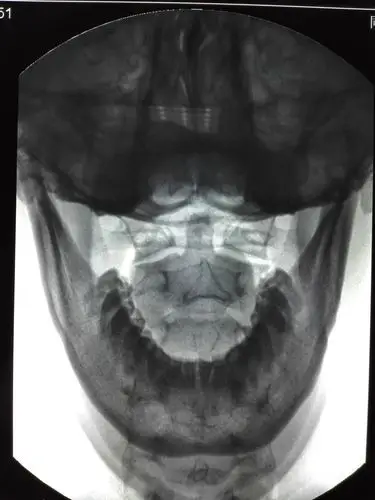

原创寰枢关节前倾错位--头痛失眠头晕颈部压迫感呼吸吞咽困难